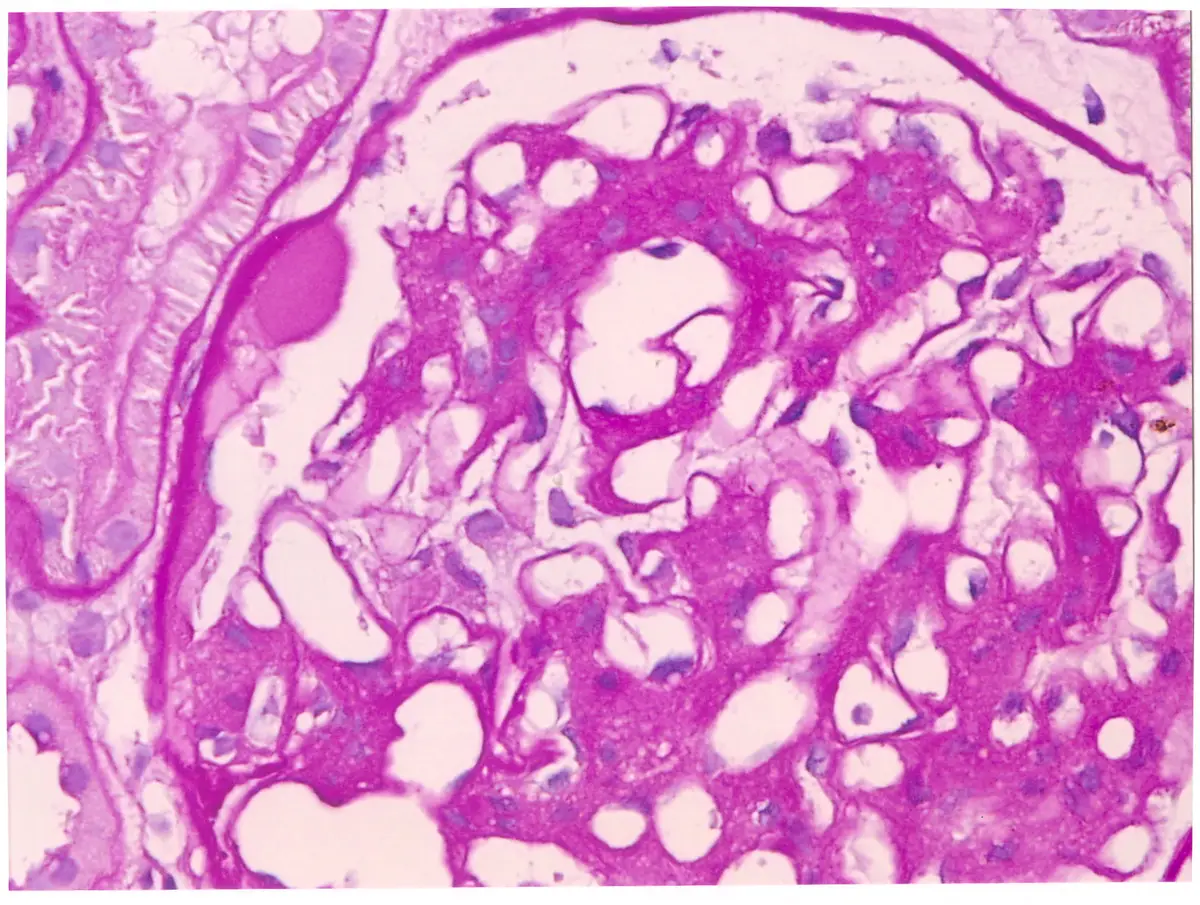

65 歲男病人呈現嚴重的蛋白尿。腎臟切片檢查顯示腎絲球病變中並無免疫複合體或補體沉積。根據本題圖示及病人臨床表現,下列腎病中何者是最可能的病理診斷?

本題考查重點在於腎病症候群(Nephrotic Syndrome)的病理診斷與鑑別,特別是結合**光學顯微鏡影像(Light Microscopy)與免疫螢光染色(Immunofluorescence, IF)**的結果來進行綜合判斷。關鍵在於辨識出糖尿病腎病變特有的組織學特徵,並利用免疫螢光陰性結果排除免疫複合體媒介的腎絲球腎炎。

影像分析:

- 染色方式:圖片顯示為 PAS (Periodic Acid-Schiff) 染色,這是一種常用於標記基底膜和間質基質(matrix)的染色法,呈現深粉紅色(magenta)。

- 病理特徵:

- 結節性腎絲球硬化(Nodular Glomerulosclerosis):影像中最顯著的特徵是腎絲球環間質(mesangium)區域出現結節狀(nodular)、無細胞核(acellular)、嗜伊紅性(eosinophilic)的硬化病灶。這就是典型的 Kimmelstiel-Wilson (K-W) nodule。

- 環間質擴大(Mesangial expansion):除了結節外,整體環間質基質也呈現瀰漫性增生。

- 基底膜增厚:微血管壁的基底膜看起來均勻增厚。

- 綜合判斷:此影